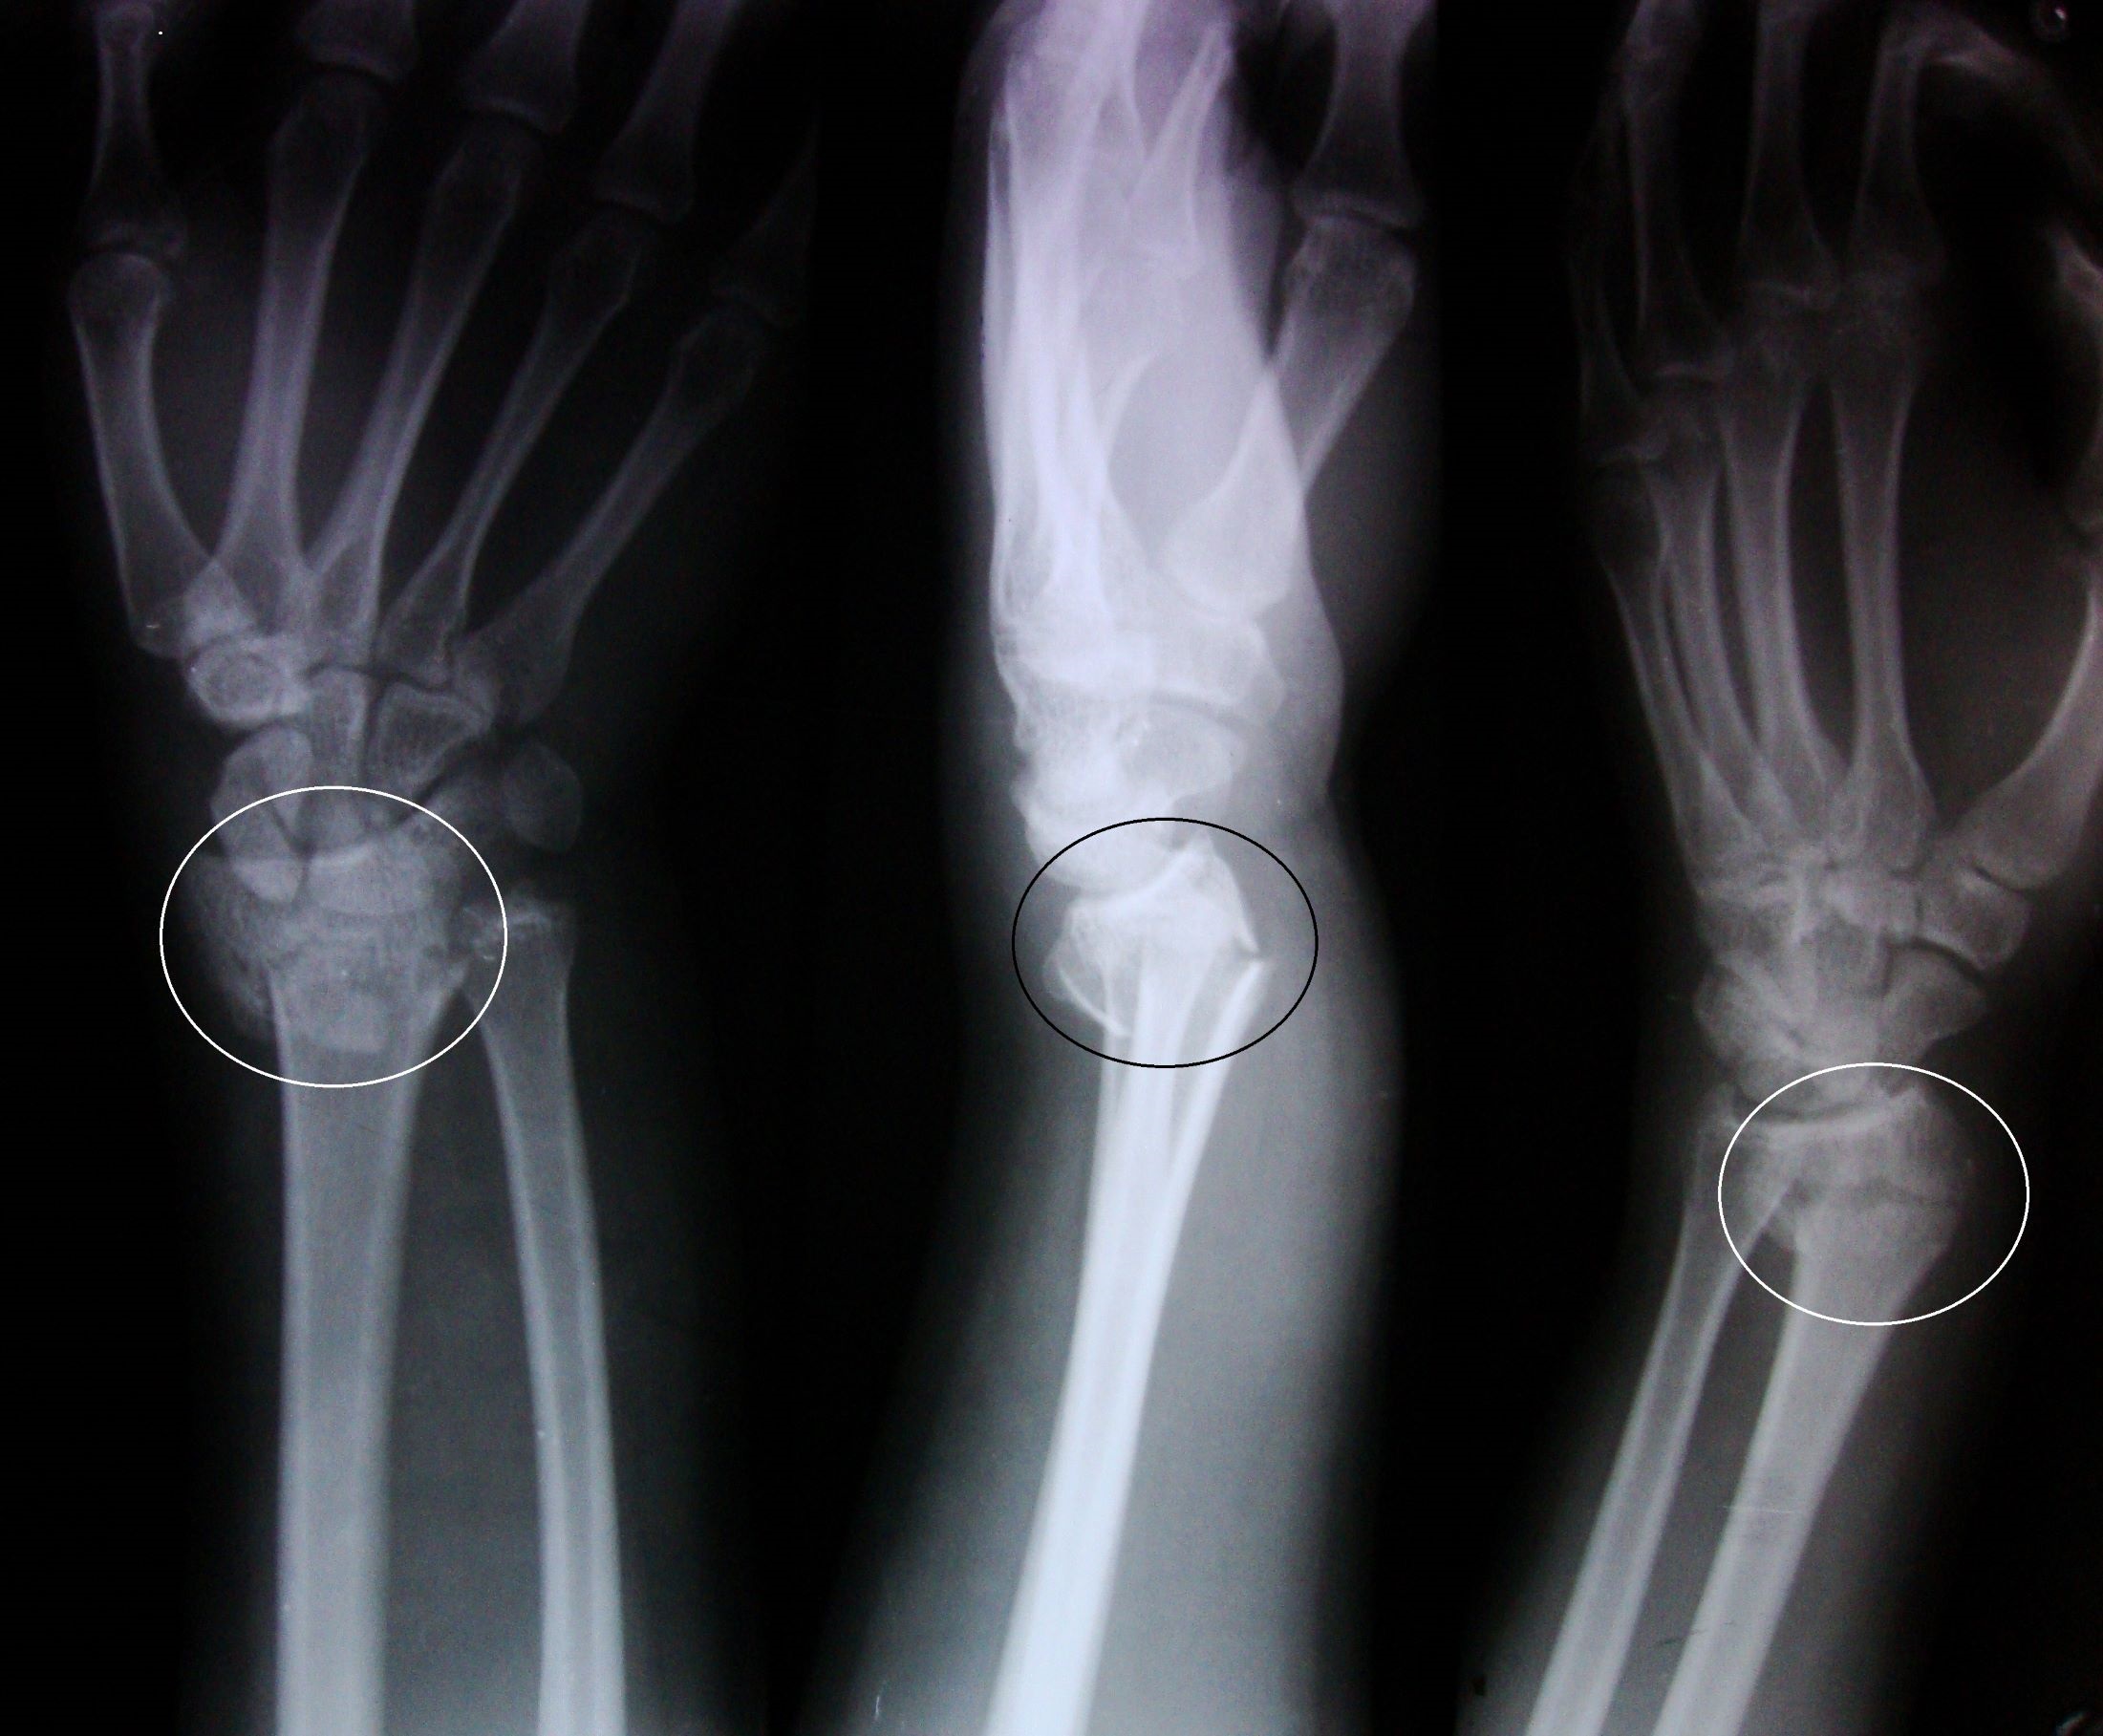

Xray of a distal radius fracture before management Download How To Prevent Distal Radius Fracture  The most common broken wrist bone is the radius. If the distal radius fracture is in a good position, a splint or cast is applied. In fact, the radius is the most commonly broken bone in the arm. You should move your shoulder, elbow and fingers regularly to prevent stiffness at these joints. Usually a cast will remain on for. How To Prevent Distal Radius Fracture.

A, B Pre operative trauma series of a distal radius fracture. C, D How To Prevent Distal Radius Fracture  Usually a cast will remain on for up to six weeks. Hss is ranked #1 in us for orthopedics. Treatment depends on many factors, such as the nature of the fracture, your age, and. The most common broken wrist bone is the radius. Hand surgeons call this a distal radius fracture. You should move your shoulder, elbow and fingers regularly. How To Prevent Distal Radius Fracture.